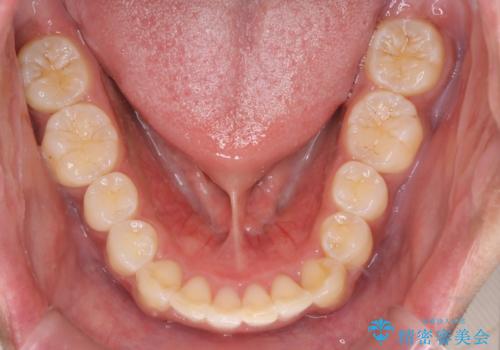

インビザラインによる出っ歯の矯正

- 出っ歯と下の歯のガタガタを主訴に来院されました。

上の奥歯を後方に移動させて、スペースを作り前歯を内側に引っ込める計画としました。

インビザラインによるマウスピース矯正で治療をすることとしました。

インビザラインをしっかり使用していただいたので、スムーズに治療をおえることができました。